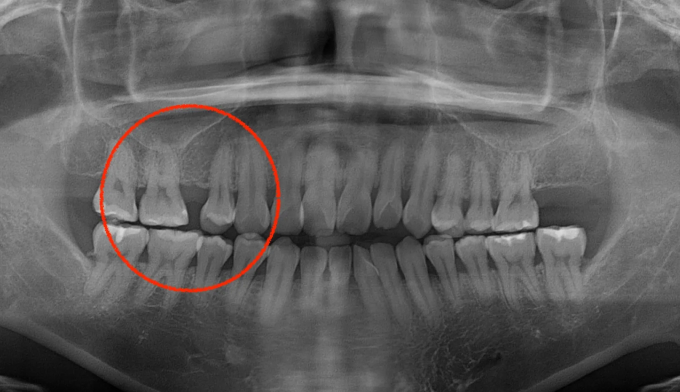

어금니가 상실된 경우, 보통 해당공간에 임플란트를 식립합니다. 하지만 보철치료에 대한 거부감이 있거나, 그 폭이 애매하게 좁은 경우, 교정치료를 통해 공간을 닫는것이 효과적인 경우가 많습니다.

해당 케이스에서는 반대쪽 어금니도 없었기 때문에 짝을 맞추기 위하여 임플란트 식립 대신 해당 공간을 교정치료를 통해 닫기로 하였습니다.

9개월만에 2개의 어금니를 전방으로 이동시켜 아래 어금니와 안정적인 교합을 형성하였습니다. 임플란트 없이 본인의 치아로 불편함없이 지낼 수 있게 되었습니다.